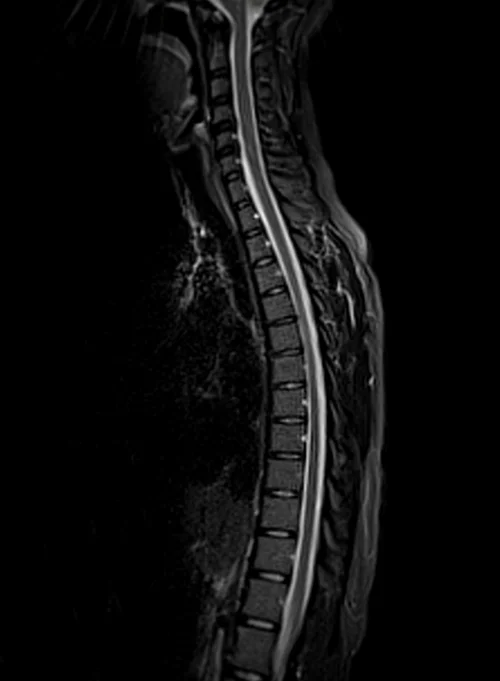

Thoracic spine mri sagittal stir images